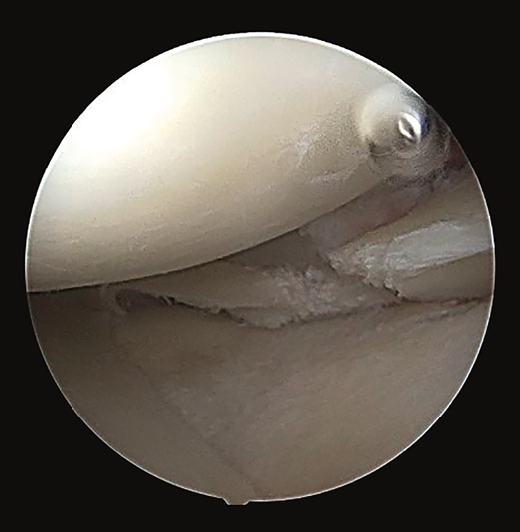

Arthroscopy confirmed the diagnosis by visualizing the avulsed root and bone fragment at medial level (Figure 4A) and the radial lesion of the external root (Figure 5). Palpation of both roots evidenced clear instability. The ACL was greatly affected, with subtotal rupture, while the PCL presented correct stability in response to palpation and testing.

reacae.28373.fs2101002-figure5.png

Figure 5. Arthroscopic view from the anterolateral portal, identifying the radial lesion of the root of the external meniscus.